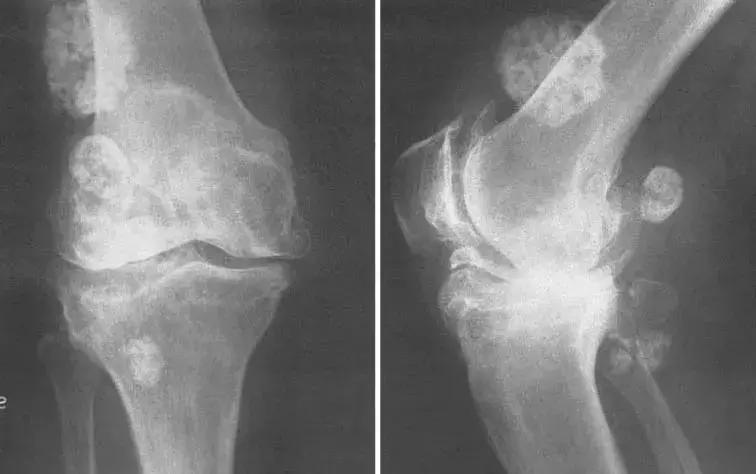

膝关节有严重的继发性骨关节炎

危及关节时,关节会被破坏,使关节慢慢畸形,譬如双手呈鸡爪状,一看便知功能尽失。

更加严重的时候,甚至还会瘫痪、骨骼破坏、肌肉萎缩,若是不及时治疗,所有内脏器官都逃不过灾厄。

类风湿导致手掌变形、关节钙化